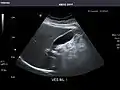

Abdominal Ultrasound (Full Exam)

STRUCTURED REPORT

(Technique: Transabdominal ultrasonography; Device: Toshiba Aplio XG)

Liver: Diffusely homogeneous and normal in echogenicity. No focal mass or contour nodularity. No intrahepatic biliary ductal dilatation.

Portal Vein: Patent main portal vein.

Gallbladder: No stones, wall thickening, or pericholecystic fluid.

Common Bile Duct: Nondilated measuring 1.3 mm at the level of the porta hepatis.

Pancreas: Visualized portions unremarkable.

Spleen: Normal in size.

Kidneys: Right and left kidneys measure 11.5 cm and 12 cm in length respectively. No hydronephrosis. Small left lower pole kidney cyst.

Ascites: None.

Aorta: Visualized portions normal in caliber, 16 x 15 mm.

IVC: Normal.

IMPRESSION:

Normal abdominal ultrasound.